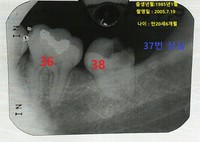

박주신을 치료했다고 주장하는 치과의사 문씨가 지난 6차 공판에서 증언한 내용이 일관되지 않거나, 치료한 내역도 일반적인 치과 상식과 다른 것으로 나타나면서, 대리인의 치아상태에맞춰 진료기록을 ‘급조’한 것 아니냐는 의혹이 제기되고 있다. 양승오 박사(동남권원자력의학원